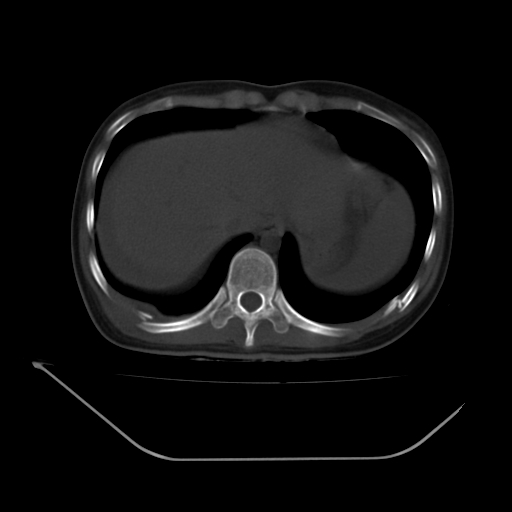

以下是引用liuyue在2008-7-19 13:02:00的发言:[br]1.肝右叶后下段及右肾挫裂伤伴腹腔积血。[br]2.右侧多发性肋骨骨折、横突骨折、右髂骨骨折伴周围软组织挫伤。[br]3.右侧腰大肌肿胀,并可见低密度影,如为气体,则肠道挫裂伤待除外。

以下是引用zhengfaming在2008-7-19 14:42:00的发言:[br]1.肝右叶后下段及右肾挫裂伤伴腹腔积血。脾脏挫裂伤待排[br]2.右侧多发性肋骨骨折、横突骨折、右髂骨骨折伴周围软组织挫伤。[br]3.右侧腰大肌肿胀,并可见低密度影,如为气体,则肠道挫裂伤待除外

以下是引用道哥在2008-7-19 16:52:00的发言:[br]肝右叶后下段及右肾挫裂伤、脾破裂伴腹腔积血。[br]2.双侧多发性肋骨骨折、横突骨折、右髂骨骨折伴周围软组织挫伤。[br]3.右侧腰大肌肿胀,并可见低密度影,如为气体,则肠道挫裂伤待除外。